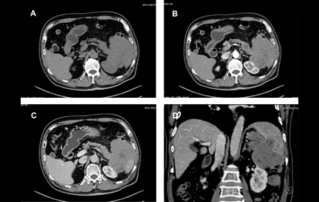

? ??? ?????? ??? ?? ? ??(cyst)? ??(etiology)?? ?????. ?????? ??? ???? ?? ?? ??? ???? ?? ?? ??? ??? ????. ?????? ?? ??? ????? ??? ? ?? ?? ?? ???? ???? ?? ? ????. ? ? ????? ??? ?? ???? ?????. ??? ??? ?? ???? ??? ???? ??? ??? ????(episiotomy) ???? ?????? ??????. ??? ??? ??? ????, ?? ?????? ?????? ?? ??? ?? 43? ??? ? ?????? ??????. ?? ? ?? ??? ?? ??(urethral diverticulum)? ?? ???? ?? MR ? US ??? Gartner?(GartnerŌĆÖs duct) ??? ??????.??? ?? ? 3?? ?? ??? ?????.

?? ?? ??? ?????(Endocavity volume convex array transducer)(DE10-3WU, Resona 7, ?????)? ??? ??? ???, ??? ?? 1/3 ?? ? ??(anterior vaginal wall)? ???? 18x14 mm ??? ?? ??(an ovoid-shaped formation) with a parietal fine suspension, ????? ??? ???? ??(non-displaced), ????,? CDI ??? ?? ?? ???? ????????. 3D ??? -? ??? ? ??(hyperechoic septa)? ?? ???? ??? ?? ??.